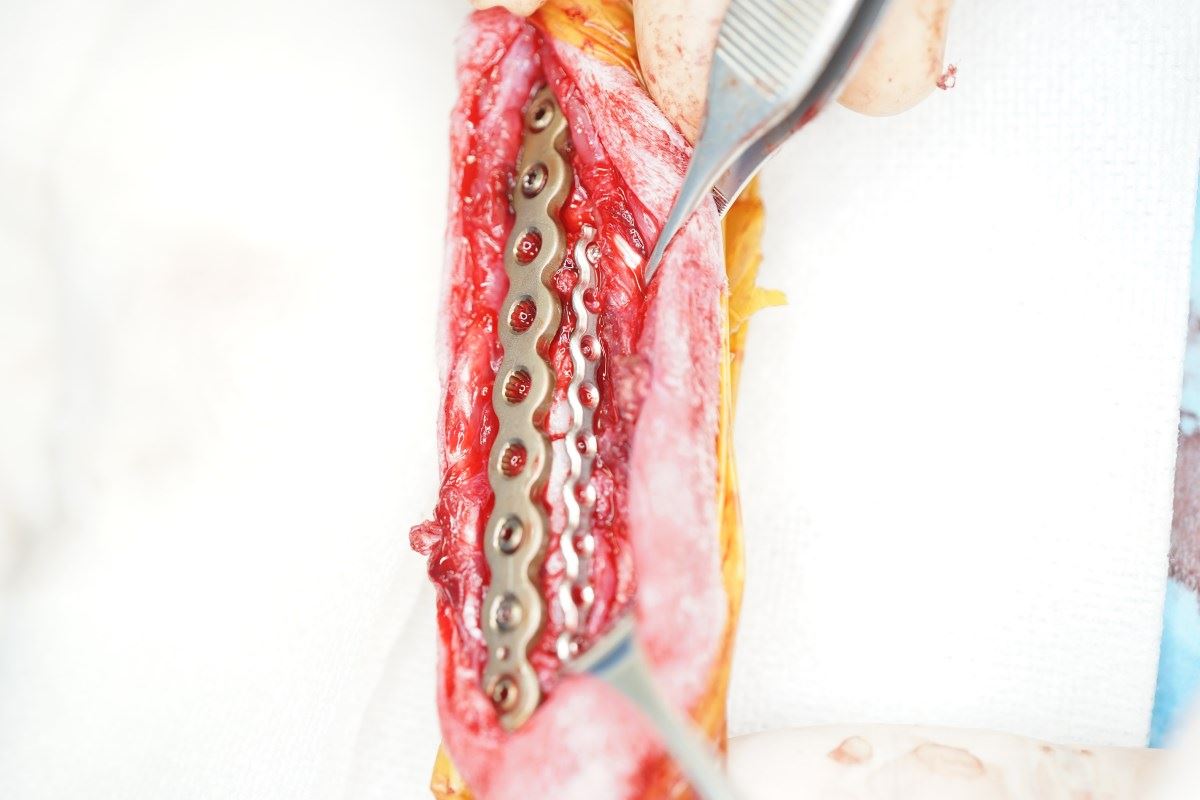

前腕骨骨折整復(ロッキングシステム)

強固かつ骨折修復過程に必要な組織を温存させた手術は治癒過程が早く、早期に運動を再開できます

強固かつ骨折修復過程に必要な組織を温存させた手術は治癒過程が早く、早期に運動を再開できます

小型犬ほど骨折が多く、治癒しにくいため、インプラントの選択が重要になってきます

ダブルプレートによる強固な内固定ではピンニングと比べると、早期に歩行が可能になります